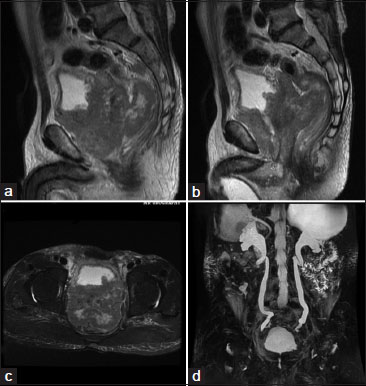

| Figure.4:MRI Urography study of Diffuse Prostatic Carcinoma showing, (a and b) sagittal T2WI images, large prostatic mass that is bulging into the urinary bladder base and pushing the large bowel loops more posteriorly with loss of fat planes between prostate and adjacent organs, (c) axial T2WI showing heterogenous isodence to hyperintense mass lesion protruding into bladder. (d) 3D MR Urography image showing hydronephrosis caused by the bladder outlet obstruction because of prostatic mass